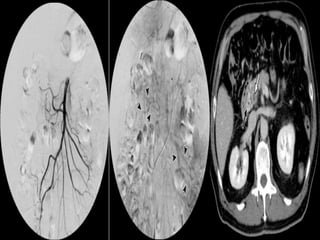

ARTERIAL OCLUSIVE ISCHEMIAVENOUS OCLUSIVE ISCHEMIA SMA THROMBOSIS SMV THROMBOSIS NO /SUBTLE BOWEL ENHANCEMENT HYPO/HYPERDENSE BOWEL WALL THINNED BOWEL WALL (PAPER THIN BOWEL ) SIGNIFICANT BOWEL WALL THICKENING NO MUCOSAL ENHANCEMENT MUCOSAL ENHANCEMENT BOWEL LOOP DILATATION ONLY AFTER INFARCTION DILATED BOWEL LOOPS WITHOUT INFARCTION LATE STAGES –MESENTERIC FAT STRANDING,EDEMA/HEMORRHAGES MARKED FAT STRANDING AND HEMORRHAGE